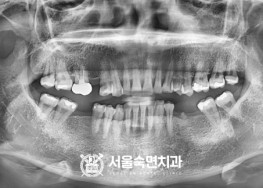

임플란트-치료-전후사진